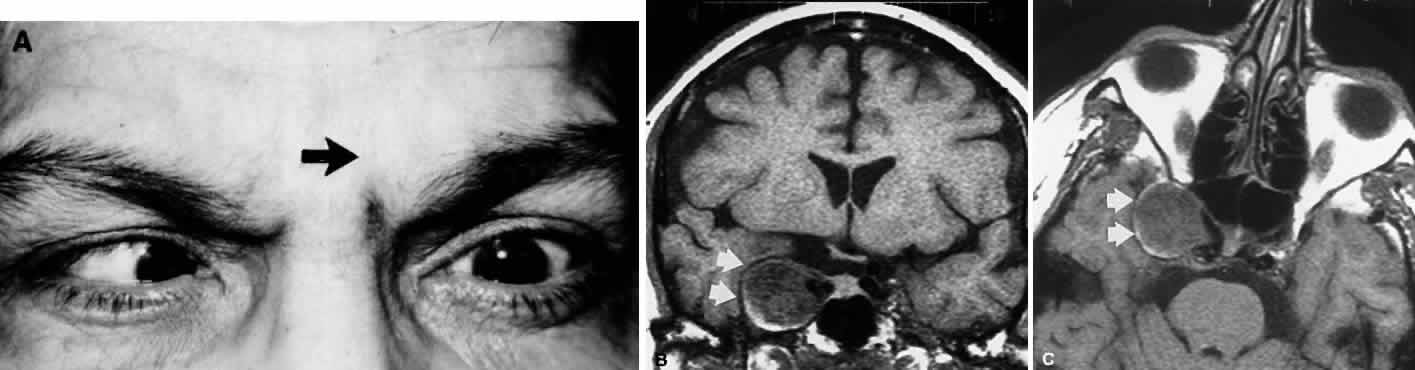

In the cavernous sinus, the abducens nerve may be involved in combination with the ophthalmic-trigeminal, third, or fourth nerves. Abducens monoparesis is frequent with cavernous sinus lesions, perhaps related to the nerve's location within the sinus, inferolateral to the carotid artery and unsupported by the dural wall of the sinus.19,20 Isolated abducens palsy occurs with carotid-cavernous fistulas (especially with spontaneous dural shunts21) and intracavernous aneurysms20 (Fig. 7), and is the earliest indication of contralateral spread of cavernous sinus thrombosis. Sixth nerve palsy accompanied only by ipsilateral Horner's syndrome also points to the cavernous sinus, since the ocular sympathetics from the carotid plexus may be simultaneously involved.22

Fig. 7. A. Chronic isolated sixth nerve palsy. B. Coronal and Axial (C) MRI sections showing large intracavernous internal carotid aneurysm (arrows).